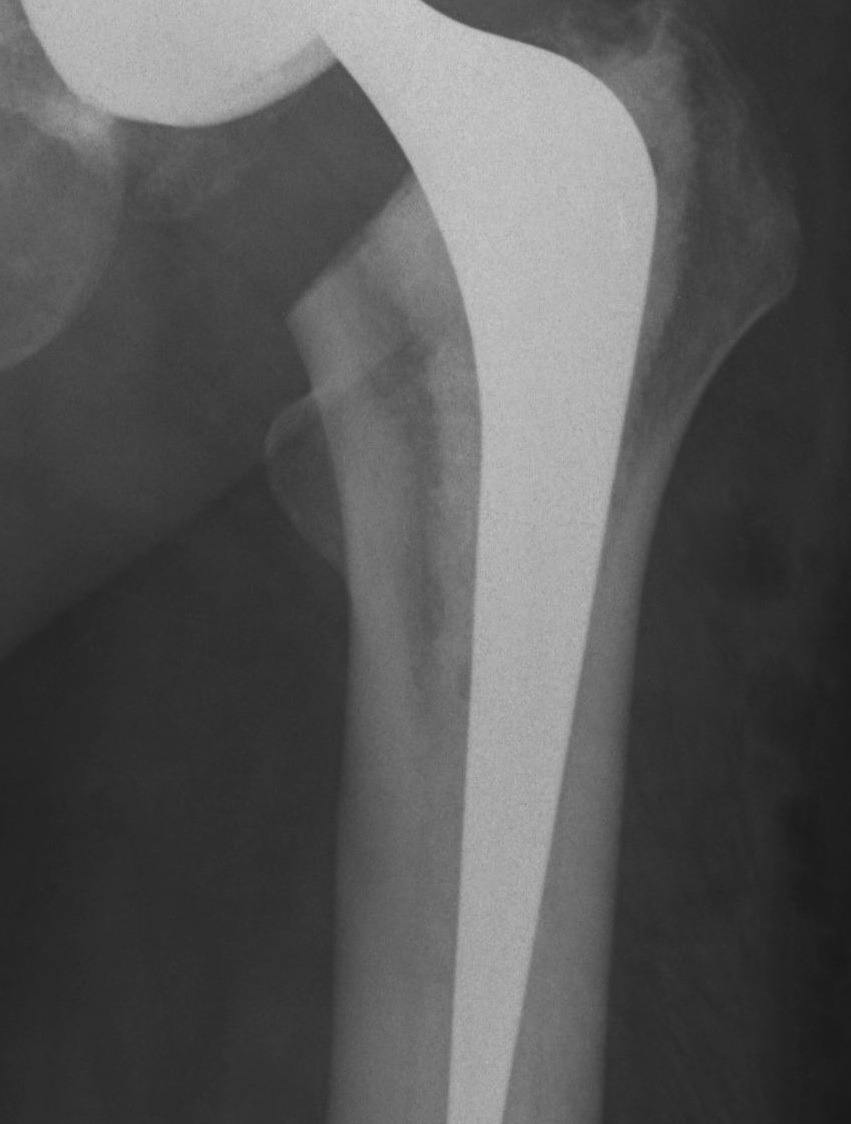

Barrack's femoral component cementation quality grading system

| Grade | Definition |

|---|---|

| A | Complete filling of the medullary canal, without radiolucent lines between the cement and the bone (white-out) |

| B | Radiolucent line covering up to 50% of the cement-bone interface |

| C | Radiolucent line covering between 50% and 99% of the cement-bone interface or incomplete cement mantle |

| D | Complete radiolucent line (100%) at the cement-bone interface and/or absence of cement distally to the end of the stem |

Grade A Grade B Grade C Grade D